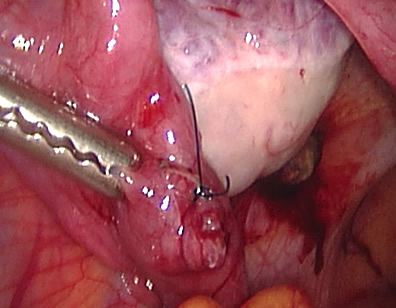

The tube was closed back and reconstructed. If a pregnancy ectopic is suspected early, laparoscopic surgery may help to preserve the tube involved.